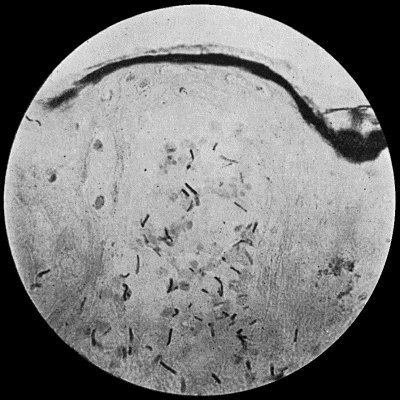

25 3.Streptococci in Pus from case of Diffuse Cellulitis

Fig. 3.—Streptococci in Pus from

an acute abscess in subcutaneous tissue.

× 1000 diam. Gram's stain.Streptococcus Pyogenes.—This organism also varies greatly in its virulence; in some instances—for example in erysipelas—it causes a sharp attack of acute spreading inflammation, which soon subsides without showing any tendency to end in suppuration; under other conditions it gives rise to a generalised infection which rapidly proves fatal. The streptococcus has less capacity of liquefying the tissues than the staphylococcus, so that pus formation takes place more slowly. At the same time its products are very potent in destroying the tissues in their vicinity, and so interfering with the exudation of leucocytes which would otherwise exercise their protective influence. Streptococci invade the lymph spaces, and are associated with acute spreading conditions such as phlegmonous or erysipelatous inflammations and suppurations, lymphangitis and suppuration in lymph glands, and inflammation of serous and synovial membranes, also with a form of pneumonia which is prone to follow on severe operations in the mouth and throat. Streptococci are also concerned in the production of spreading gangrene and pyæmia.

Division takes place in one axis, so that chains of varying length are formed (Fig. 3). It is less easily cultivated by artificial media than the staphylococcus; it forms a whitish growth.